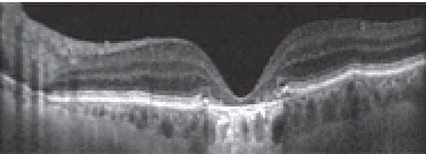

These vitelliform lesions in AOFVD result from a buildup of lipofuscin, the product of undigested photoreceptor outer segments. The lesions may gradually enlarge, and then decrease in size, resulting in an atrophic RPE and visible disruption in the IS/OS interface (see Figures 3a and 3b).7 Photoreceptors are susceptible to photo-oxidative damage, while phagocytosis by the RPE prevents toxic accumulation of damaged material in a healthy retina.8

Vitelliform lesions appear as fluffy, dome-shaped material on OCT,9 and may display hyperfluorescence on FA.10 At this time, there are no specific treatments for AOFVD.11 While patients are encouraged to take similar precautions as with AMD (nutrition, smoking cessation), correct diagnosis is crucial to offer proper counsel and additional resources to promote a high quality of life.2